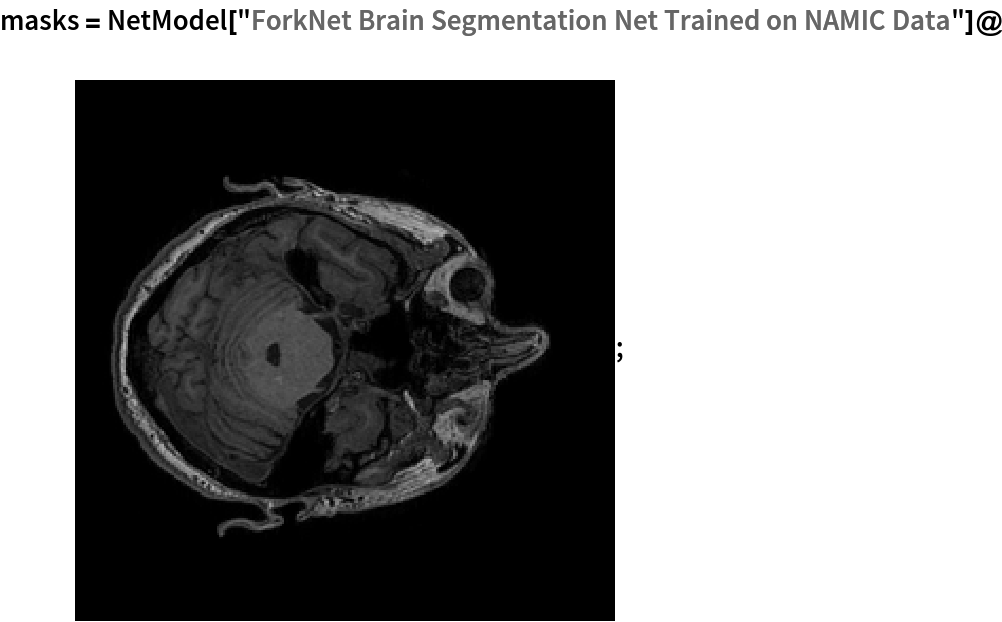

Obtain the default segmentation masks for a given image:

In[5]:=

(* Evaluate this cell to get the example input *) CloudGet["https://www.wolframcloud.com/obj/f2456b07-2f56-4614-b2fb-41ab4b010e8c"]